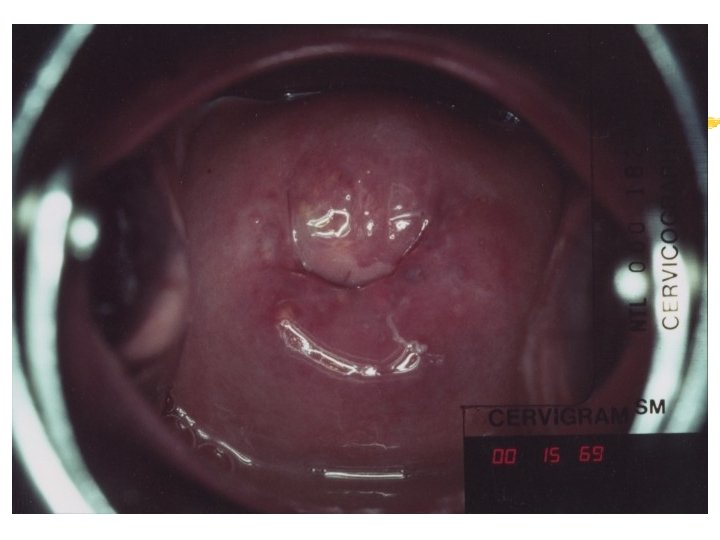

HPV infection Condyloma Accuminata Exophytic Frond like surface Lesion may be single or multiple Located within or outside the transformation zone

HPV infection Subclinical HPV Flat lesions undetectable naked eye Best assessed after acetic acid application Shinny, snow-white lesions Irregular outline Satellite lesions beyond the transformation zone Strong or partial uptake of Lugol’s iodine

Cervicography: This is NOT Colposcopy High-quality colposcopic-type photography of the cervix Cervicoscope - Hand-held camera with a macrolens and a ring-flash Cervicogram - 35 -mm photo slide is taken Principles Recognition of lesions by means suitable magnification and illumination Fix up the problems of colposcopy 1. a less expensive form 2. noninvasive method 3. do not require expert skill

Procedures of cervicography A) Taking a 35 -mm cervicogram (1) Insert speculum and open as wide as possible … expose an entire cervix and upper vagina (2) Apply first application of 5% acetic acid by dabbing … cleanse the cervix of blood and mucus (3) View the cervix through the cervicoscope … allows time to begin taking epithelial change (4) Apply second application of acetic acid. (5) Take two cervicogram pictures B) Developing the images C) Interpreting a magnified image that was projected on the screen (1) Negative if no definitive lesions are visible (2) Atypical if there was evidence of acetowhite lesion of doubtful significance (3) Positive if there was evidence of a minor or major-grade lesion or cancer